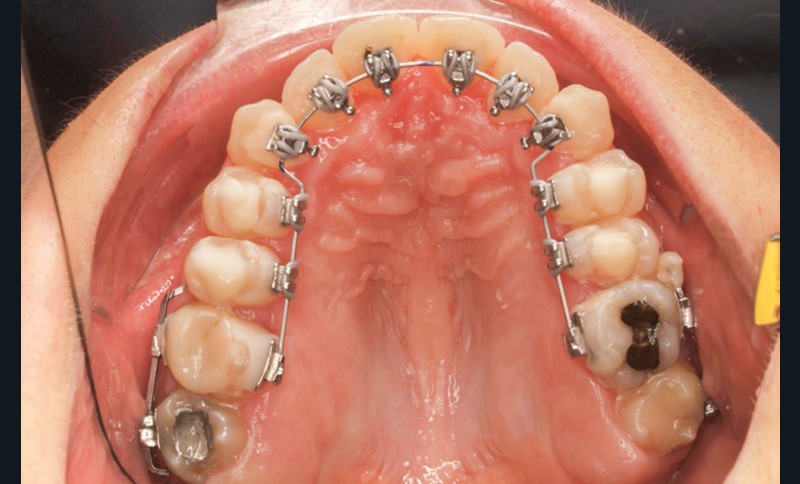

- Troisième rendez-vous (fig. 2c) : les arcs NiTi .014 sont religaturés pour améliorer le nivellement-alignement.